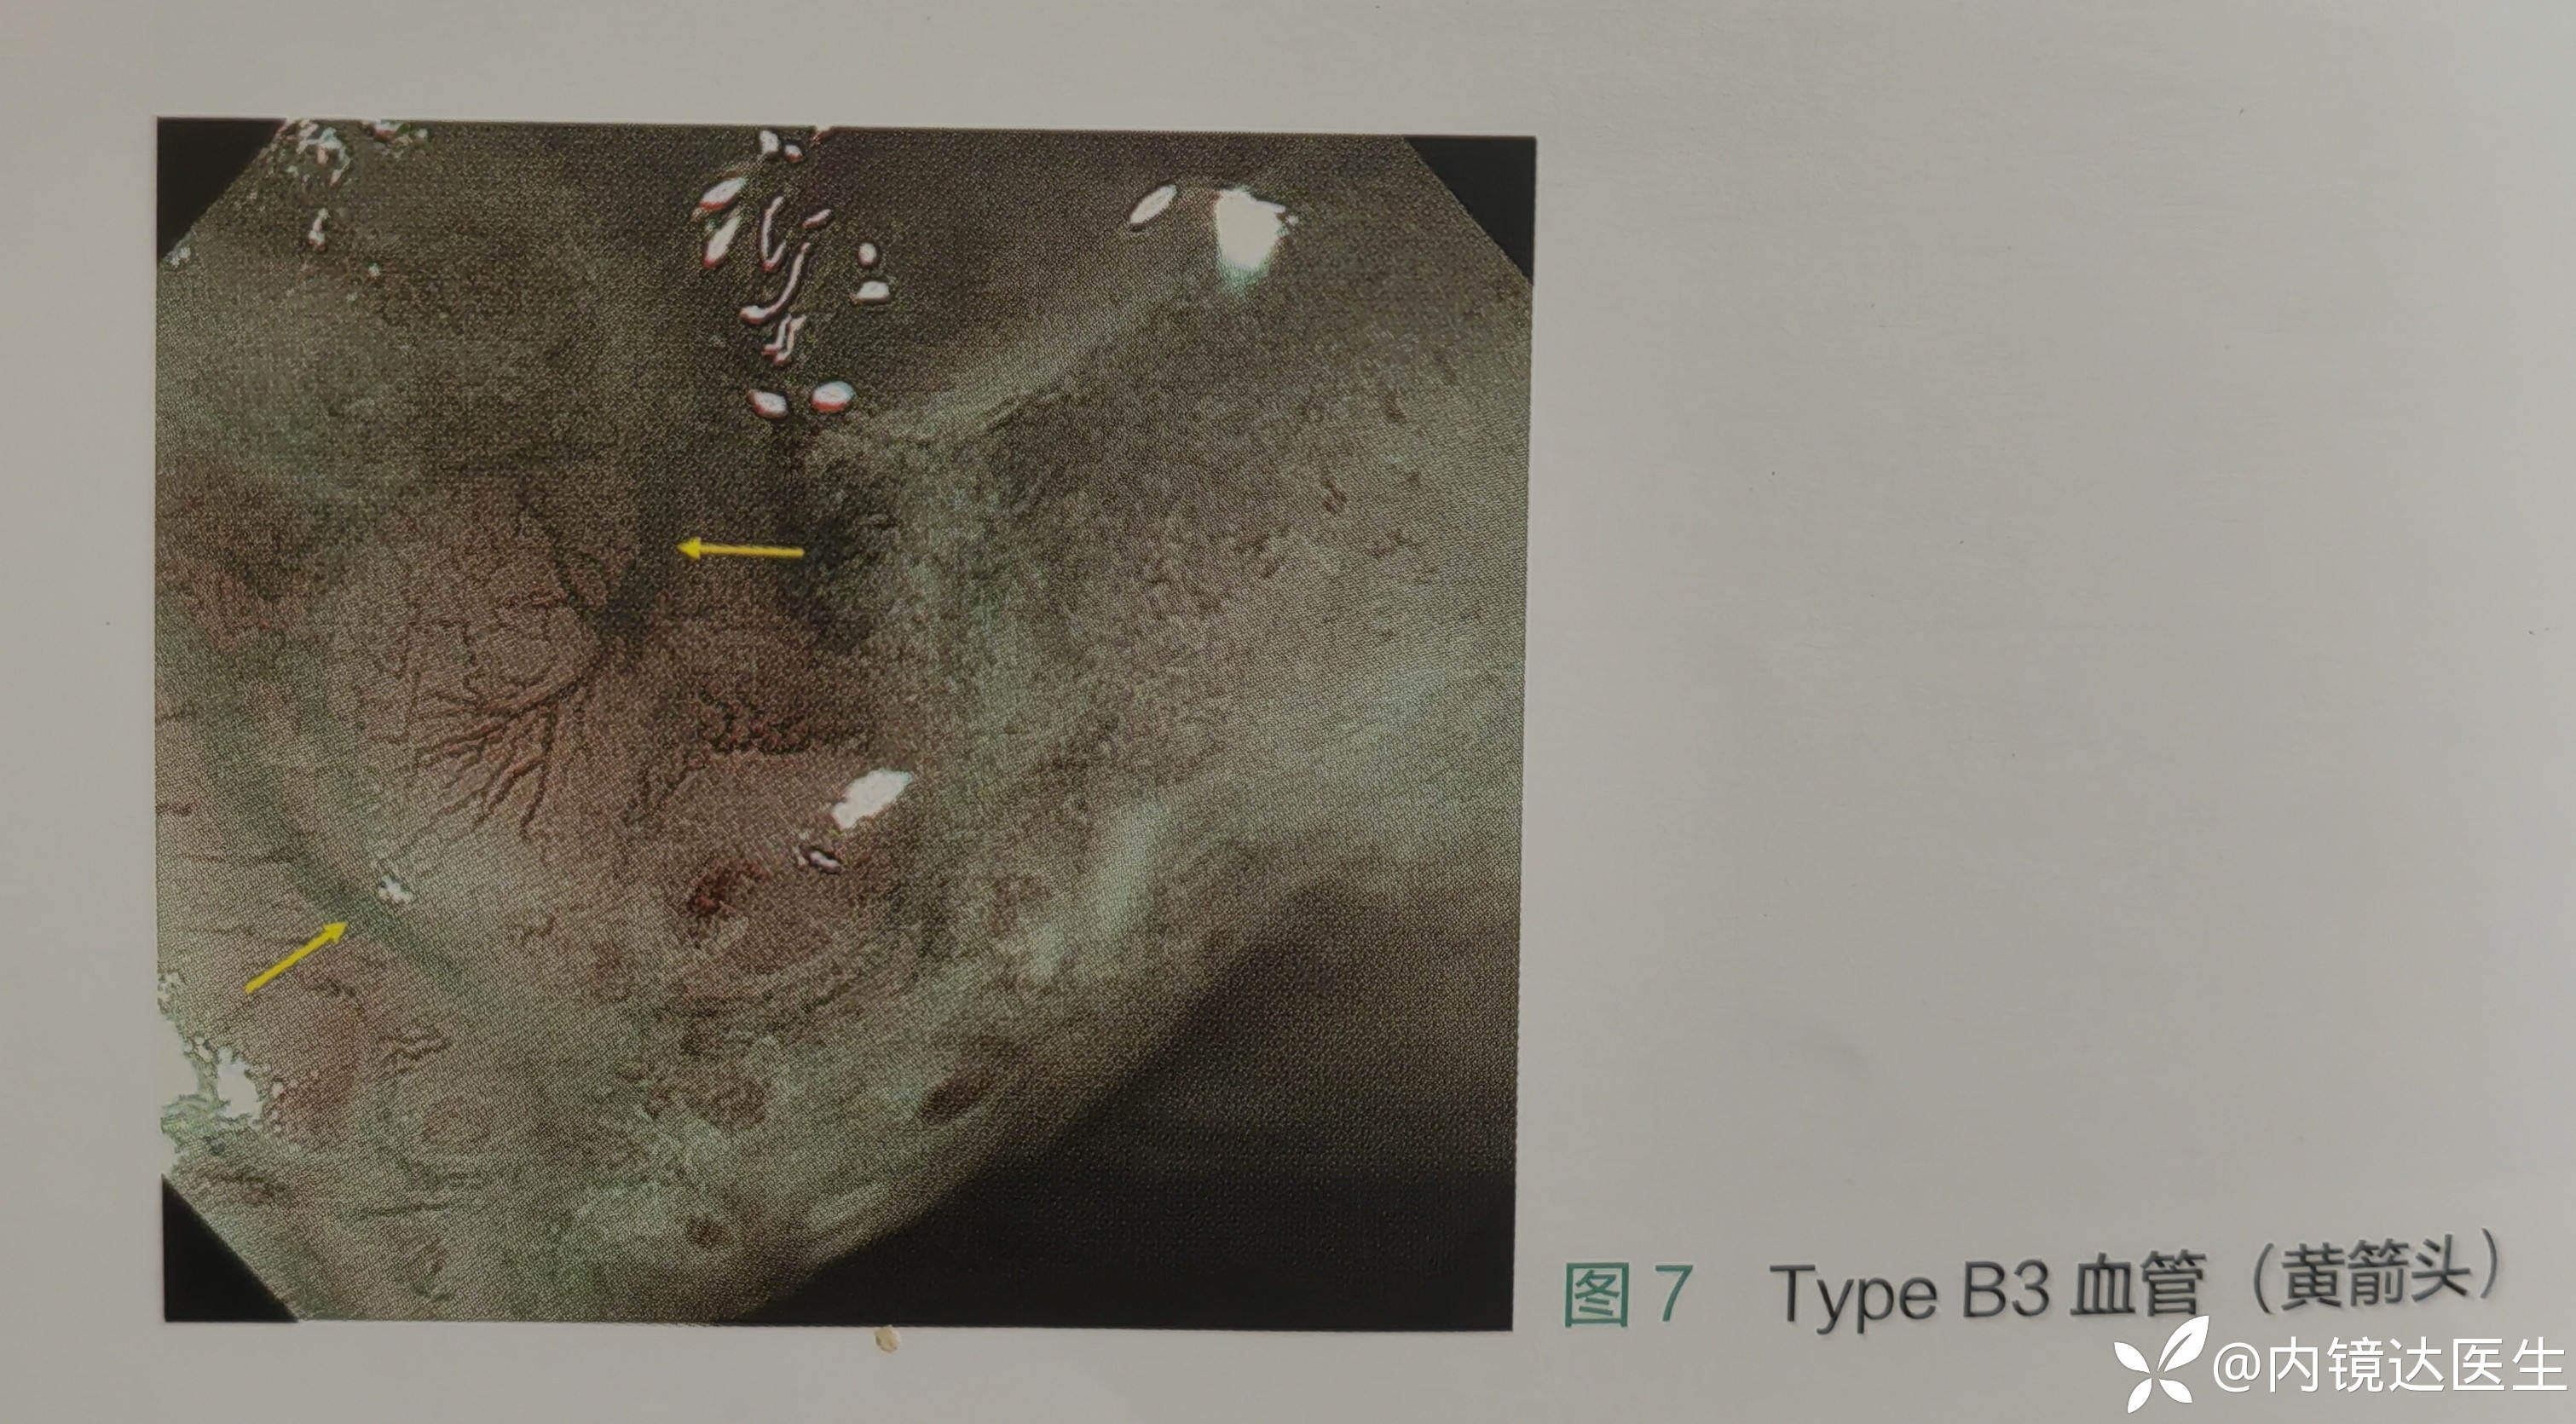

B3 高度扩张增粗不规则的血管(约为B2血管的3倍以上 血管直径超过60um),提示SM2以深,建议外科 (阳性预测率和阴性预测率均>90%)